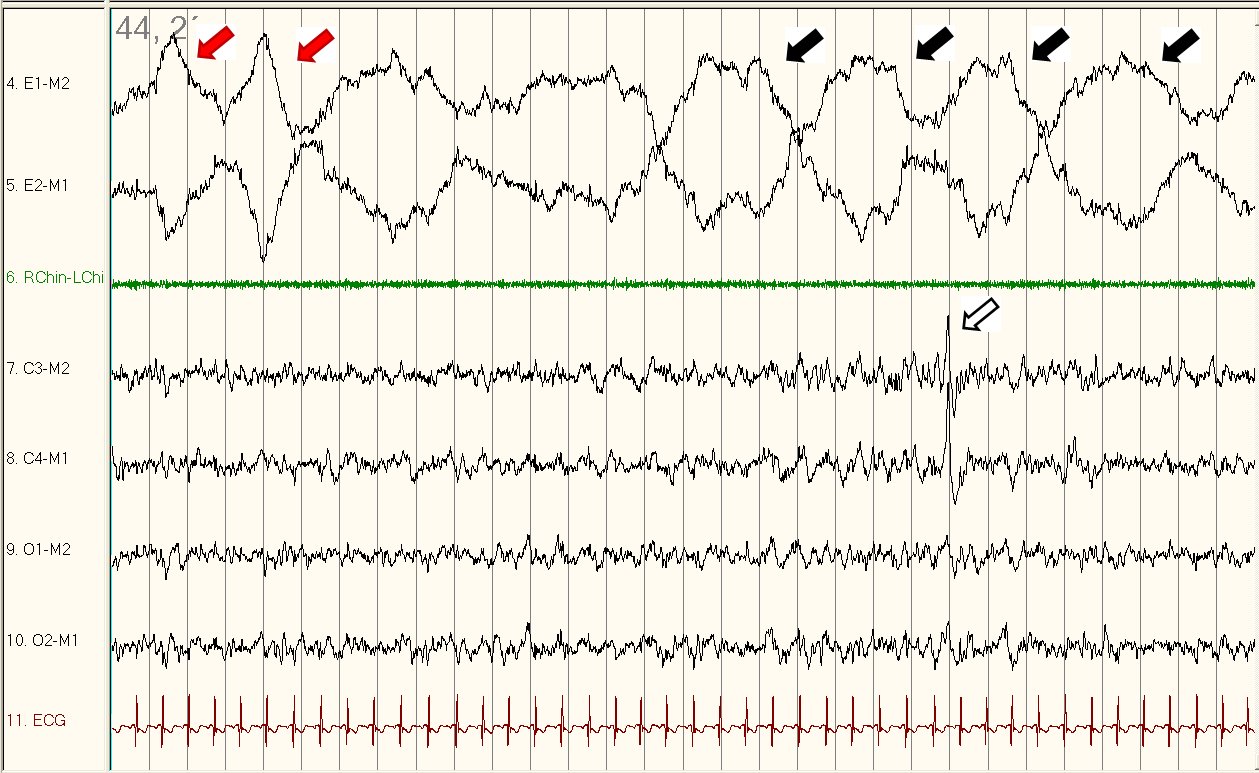

Figure 1

Figure 1 displays a 30-second tracing of stage N2 sleep with two rapid eye movements (red arrow) and a run of slow rolling eye movements (black arrows) on the electrooculographic (EOG) channel consistent with the use of Fluoxetine or another selective serotonin reuptake inhibitor (SSRI). Note that despite the rapid eye movements, the K complex (white arrow) seen on electroencephalogram (EEG) as well as the presence of muscle tone on chin electromyogram (EMG) indicates the eye movements are not part of stage REM sleep. As a comparison, Figure 2 provides a representative example of normal REM sleep in this patient with muscle atonia on chin EMG.